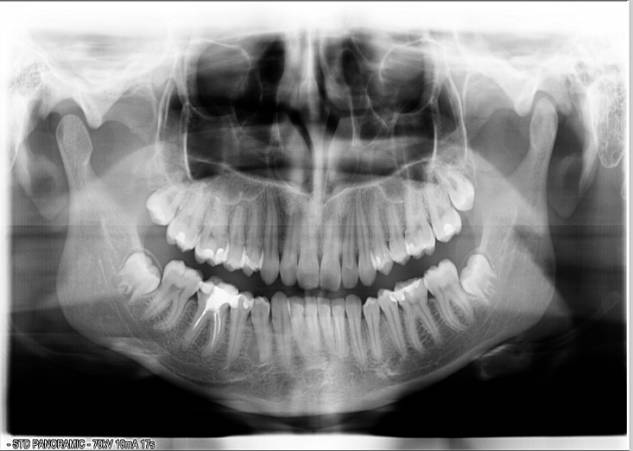

It was recommended for Patient K to do the

panoramic radiography. According to the panoramic radiography and examination

of dentition the following was found: changes in the shape and structure of the

head of the TMJ on the left, dystopia of teeth 18 and 28, lack of space for

impacted teeth 48 and 38, malocclusion in the frontal area due to reduced lower

jaw. The bite was deep and prognathic (second class first subclass

classification Engle). Teeth examination revealed: photopolymer restoration of

teeth 17, 16, 26, 27, 36, 35, 45, 46 and 46, and endodontic treatment of a

tooth 46. Established that a violation of occlusal relationship of the teeth of

the upper and lower jaw, the violation of a uniform distribution of masticatory

forces in the distal parts of the dentition (Fig. 1).

Figure 1

Panoramic radiography of patient K prior to treatment in 2008